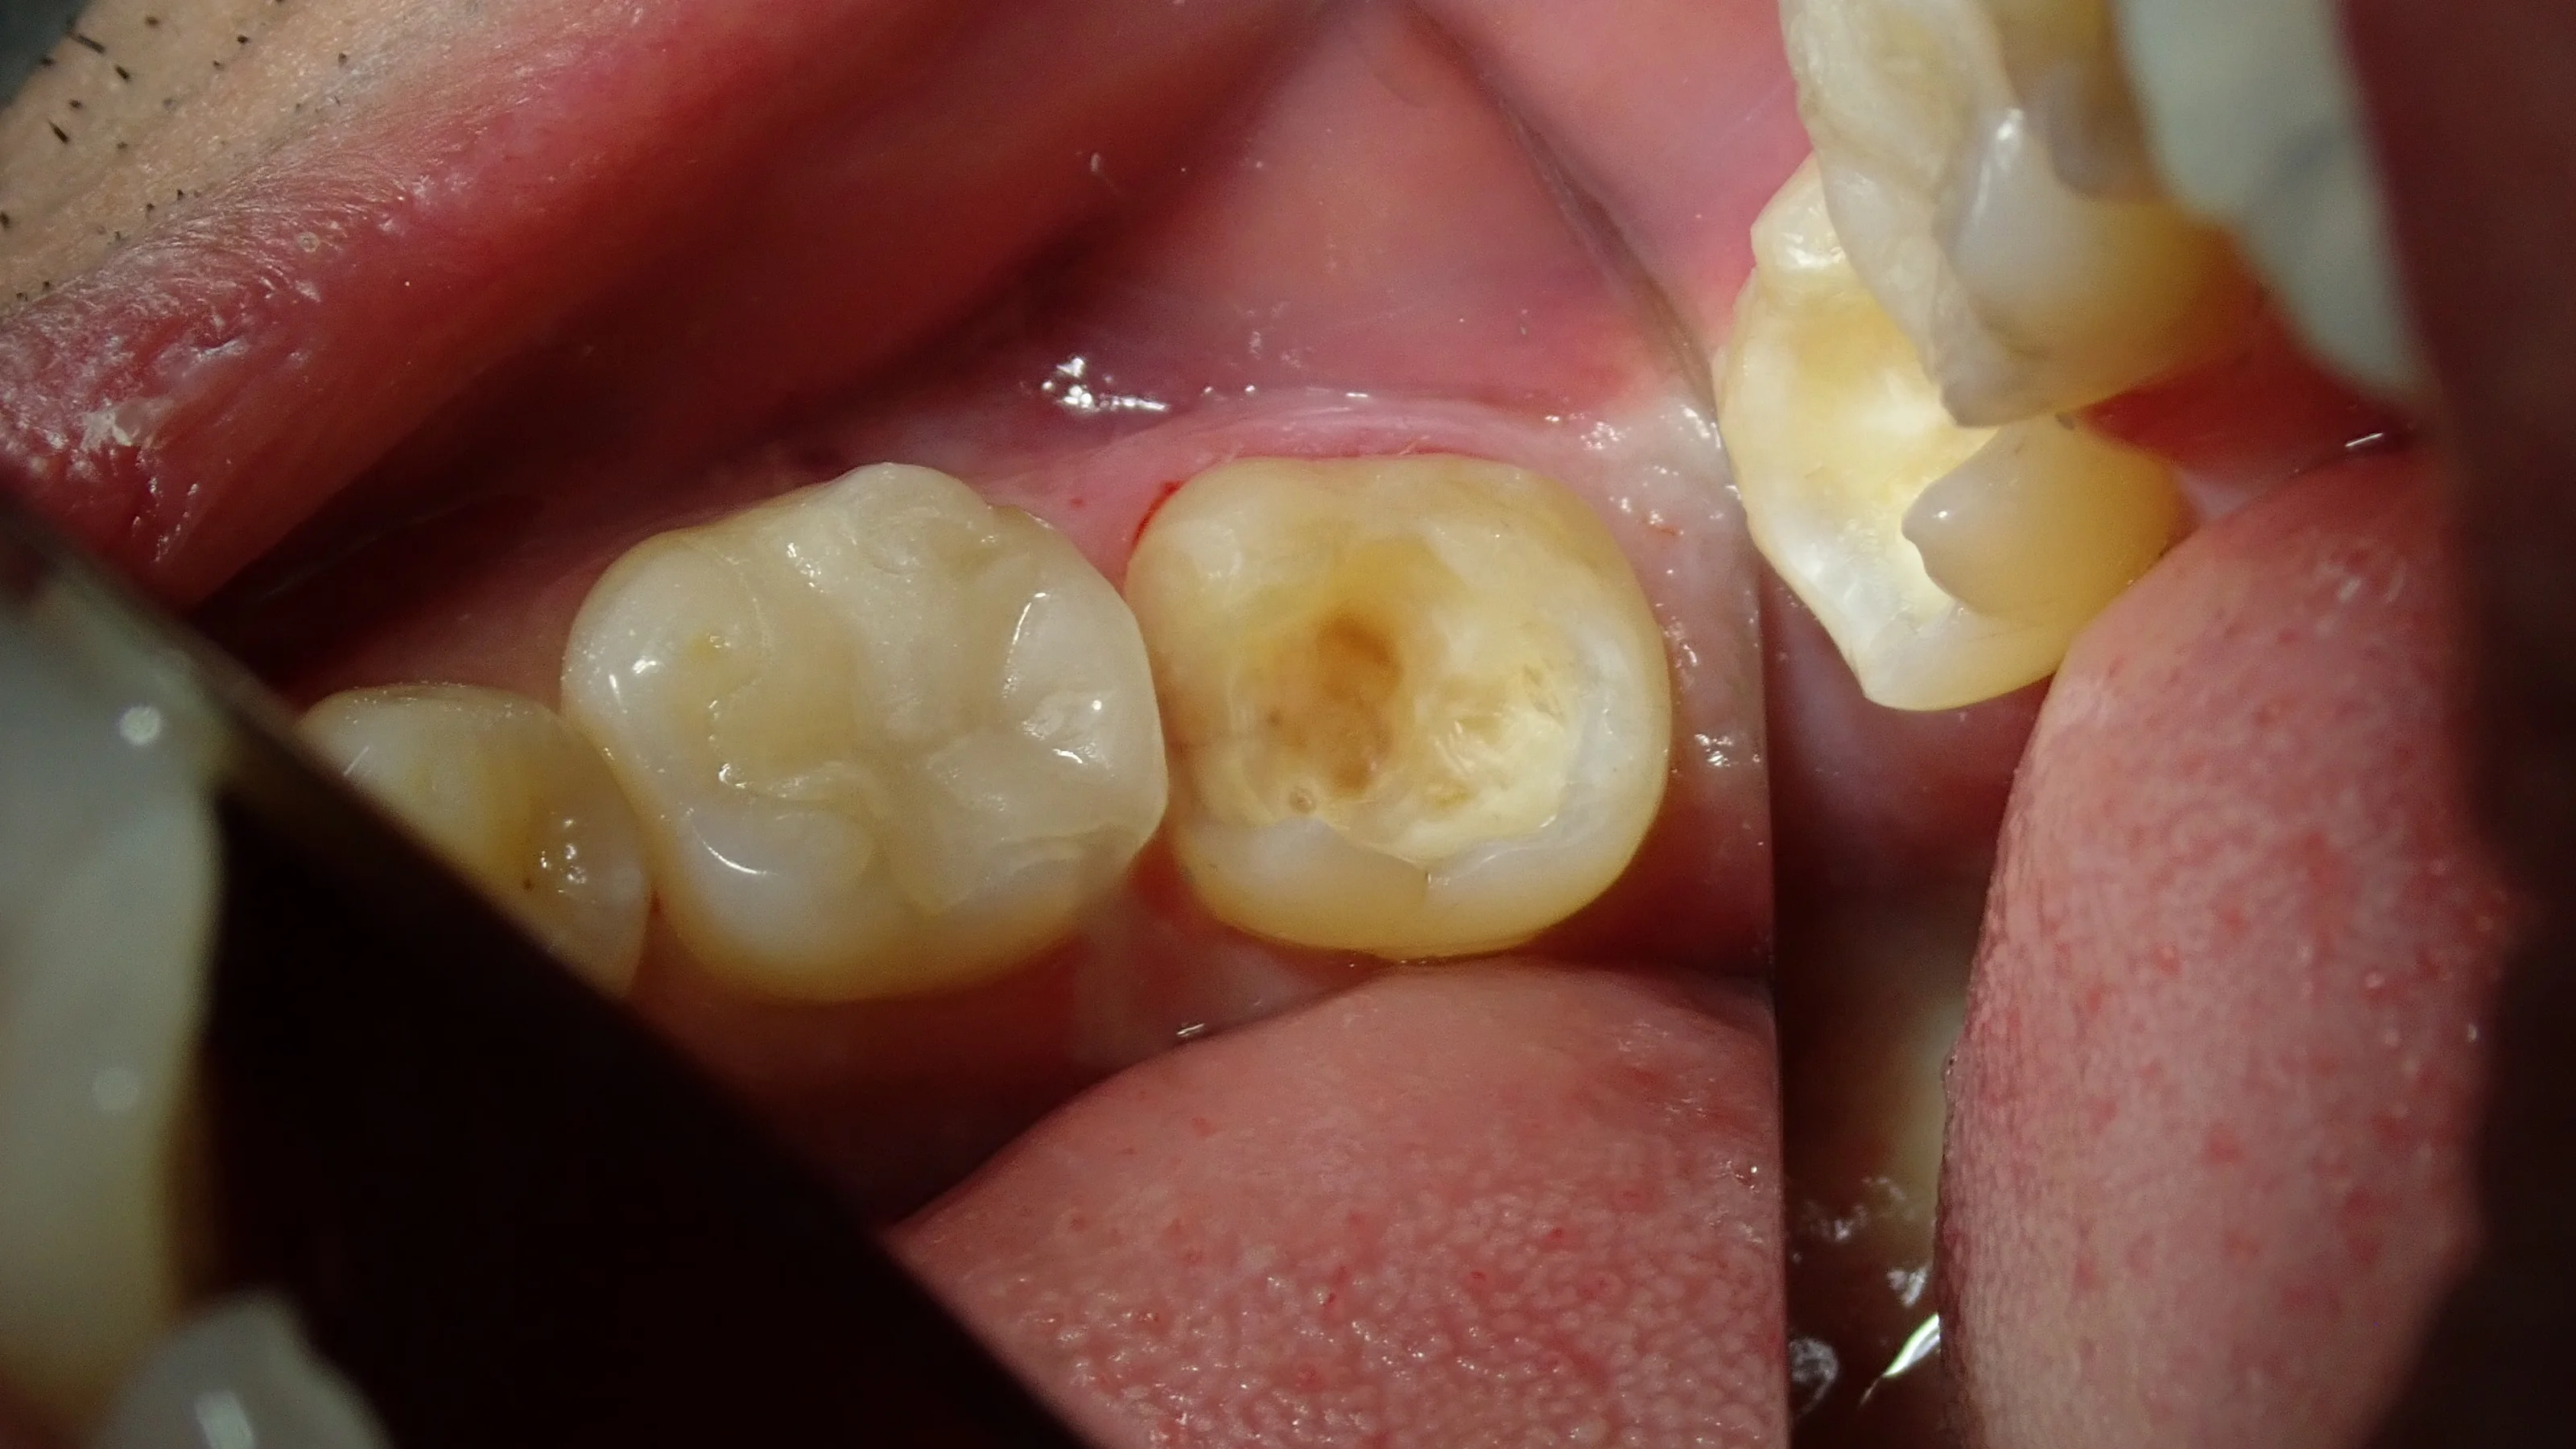

まずは術前から。

左下奥の白い詰め物|坂寄歯科医院(取手市藤代)

元々は金属の詰め物が詰まっていたとのことでした。

外れた下が黒くなっていて、大きな虫歯があるのが分かりますね。